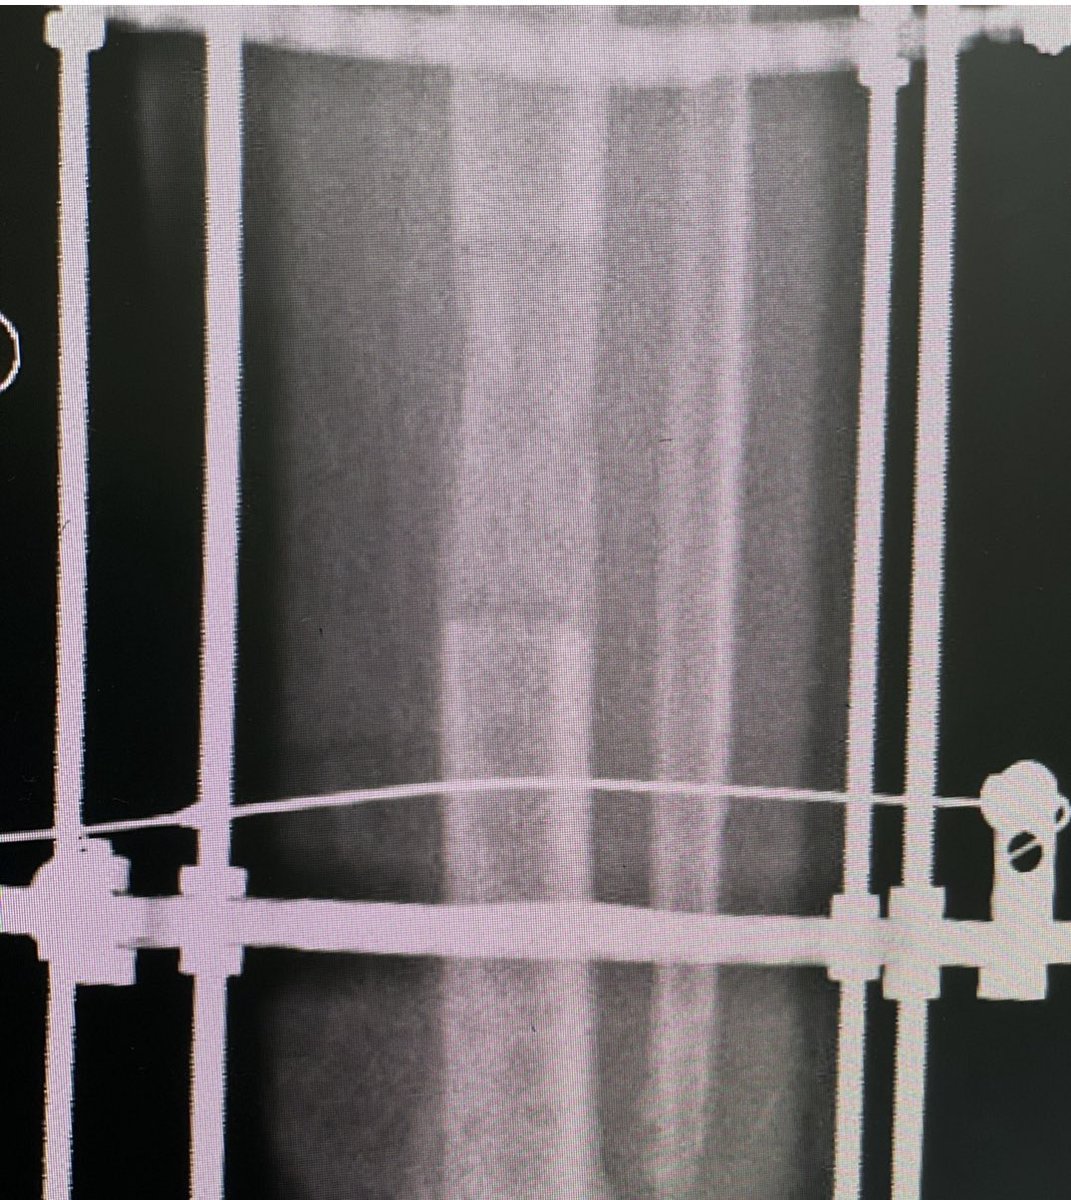

🔹بعد الانتهاء من التطويل يبقي المريض في الجهاز حتي يتم تكلس العظم بشكل جيد

🔹يتم التطويل عن طريق عده اجهزه:

خارجيه/ والاشهر جهاز اليزاروف او الجهاز الحيزي الحلقي TSF او الاجهزه الجانبيه كجهاز اورثوفكس